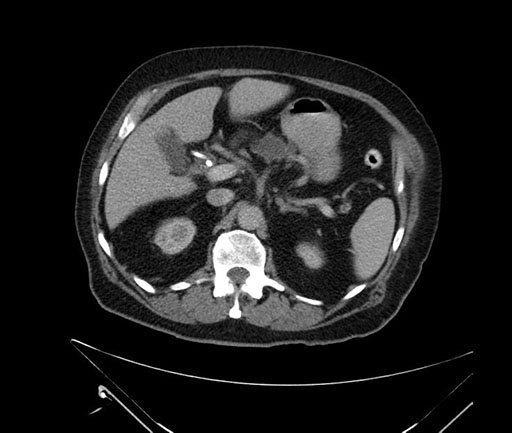

Imaging Analysis

Look through the patient's CT scan to identify any areas of concern for the necessary procedure.

Based on your CT findings, which issue(s) would give reason for "planned slowing down moment(s)" in this case?